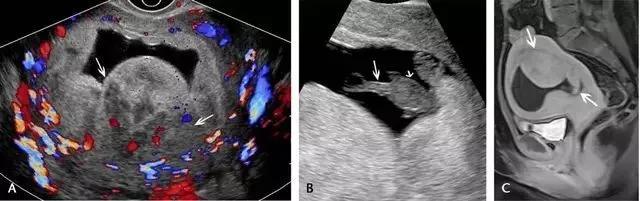

胎盘附着异常:包括胎盘粘连、胎盘植入及胎盘穿透(图 11)。胎盘粘连指胎盘组织向子宫肌壁延伸,但并未对其构成实质性的侵袭,占所有胎盘附着异常的75%。

胎盘植入指胎盘组织已侵入子宫肌壁,但并未突破浆膜层。穿透指不仅侵入肌壁,且已突破至浆膜层之外,可导致子宫的毗邻器官如膀胱、肠管及腹壁受累。超声是本病的主要显像方法,在临床高度怀疑本病或超声检查为阴性或不确定时,可使用 MRI(图 12 和图 13)。

图 11 为胎盘附着示意图 ,自最左图向右分别为正常、粘连、植入、穿透

图 12 示胎盘粘连:A 为孕 32 周患完全性前置胎盘(此图未显示)孕妇的子宫前壁横切面(线阵探头所得),可见肌壁由上至下、向膀胱子宫陷凹方向逐渐缺乏、变薄(短箭头所示)。B 为另一孕妇的冠状位 MRI,孕期经常性左腹痛,超声考虑胎盘粘连,长箭头示胎盘下方的低信号肌壁由左向右逐渐变薄。此 2 例均在剖腹产时被证实为胎盘粘连

图 13 示合并有完全性前置胎盘的胎盘穿透,患者有 2 次剖宫产病史:A 为子宫纵切面,箭头示肌壁逐渐变薄、子宫与膀胱之间的界限模糊,胎盘下的闲置空间消失(B :膀胱)。B 为同一患者的子宫矢状面,箭头示大量不规则紊乱血流向肌壁延伸。图 C 为另一孕妇 28 周时的矢状位 MRI,可见前次剖腹产瘢痕上缘存在胎盘对子宫前壁的侵犯、肌壁连续性局部中断(箭头)